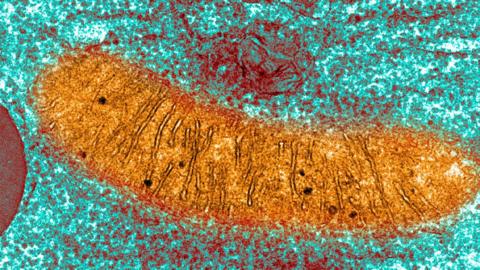

Mitochondria are tiny structures inside nearly every one of our cells. They are the reason we breathe as they use oxygen to convert food into the form of energy our bodies use as fuel.

A picture of a mitochondrion taken with a microscope - there are up to half a million in a fertilised egg.